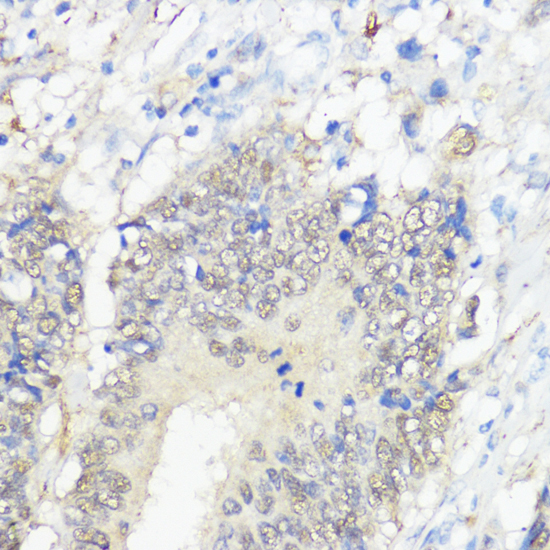

(Immunohistochemistry of paraffin-embedded human colon carcinoma using GPX2 antibody (AAA281453) at dilution of 1:100 (40x lens).Perform microwave antigen retrieval with 10 mM PBS buffer pH 7.2 before commencing with IHC staining protocol.)